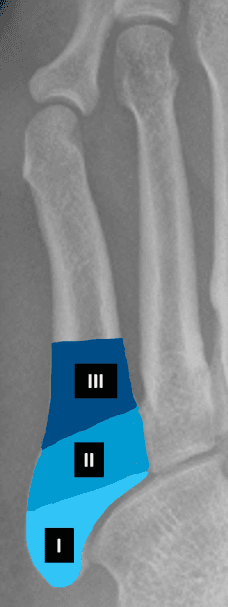

Jones brudd i 5. metatars

Denne bruddtypen er mindre vanlig enn tennisbrudd, men er mer problematisk å behandle. Det er et tverrbrudd ca. 1,5-3 cm lengre ut i metatarsen, det vil si i skaftet til 5. metatars. Bruddet oppstår ofte ved indirekte skade (under trening). Feilstillingen ved dette bruddet tenderer til å øke under vektbelastning. Det er ganske vanlig at bruddet ikke gror, noe som kan skyldes at man har belastet foten for tidlig. Behandlingen er som regel støvelgips og avlastning i 7 uker. Pasienter med dette bruddet utvikler ofte (35-50%) vedvarende manglende tilheling og trenger bentransplantasjon og intern fiksasjon (pinne, streng eller skrue). Noen velger operativ avstiving fra starten av hos profesjonelle idrettsutøvere. Ved manglende tilheling gjøres operasjon der man bruker beintransplantat.